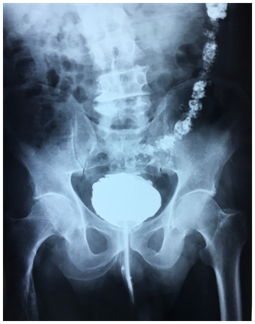

An antibiotherapy was started and retrograde and urinary uretro-cystography was performed. Retrograde cystography showed diverticular bladder with opacification of the sigmoid colon up to the half of the transverse colon (Figure 1) (Figure 2).

Figure 2 Profile view of retrograde urethrocystography showing opacification of colon until half of his transverse portion.